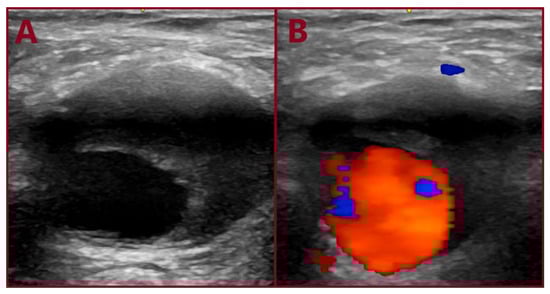

Show Figures

Figure 1